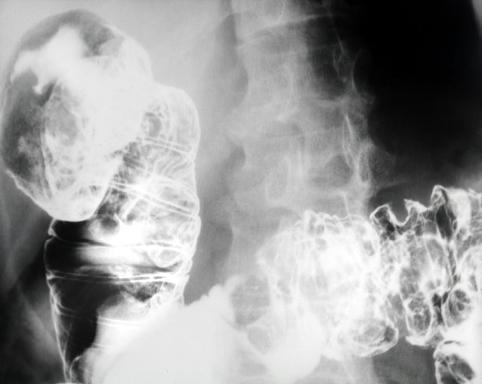

症例提示(所在地,施設名等): 東京都・ 国立がんセンター中央病院と九州がんセンターの共同作成

症例登録日 2003/08/08

画像数 28

性別 男性

年齢 55-59

取得年代 1970-1974

画像ID:5499

疾患(病理主体)の分類悪性リンパ系腫瘍/悪性リンパ腫

部位(臓器別)十二指腸/2つ以上

検査方法X-P

病変の最大径(ミリ)25〜29

多発腫瘍(同一臓器)有(同時性)

多重腫瘍(他臓器)有(同時性)